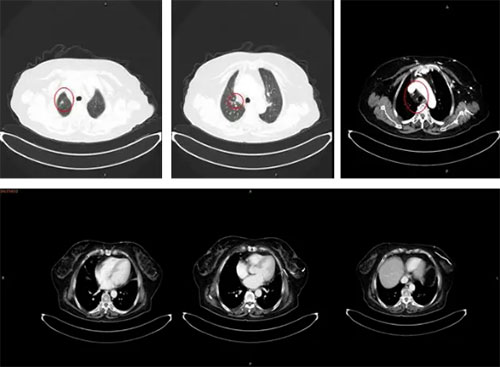

以下为影像学资料

2017年5月医院治疗前胸腹部强化CT:右肺上叶占位、右肺多发小结节、纵隔淋巴结肿大并增强扫描时强化。

胸腹部强化CT:右侧胸膜条状、结节状增厚并强化。提示胸膜转移。

2017年10月治疗后患者CT提示病灶明显缩小,胸膜广泛转移病灶消失。